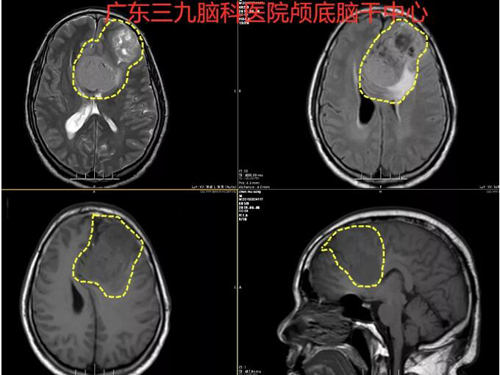

图1:术前MR示左侧额部-镰旁巨大占位性病变,长T1混杂T2异常信号影,FLAIR序列呈高、低混杂信号,其内示血管流空信号影,大小约82mm×47mm,邻近胼胝体、右侧额叶明显受压,邻近蛛网膜下腔间隙稍增宽。考虑脑膜瘤可能性大,建议补充增强检查及ASL;2.脑白质少许变性灶;3.双侧大脑前动脉受压右移及上矢状窦前份局部轻度受压、信号减弱,考虑肿瘤压迫所致;4.左侧大脑前动脉A1段缺如,考虑发育因素所致